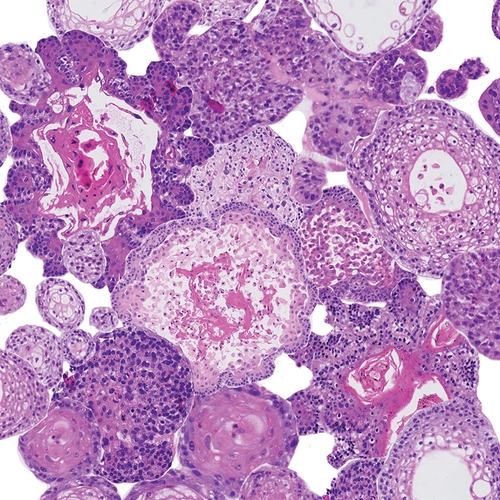

Een close-up van een microscoop; organoiden hoofd-halskanker